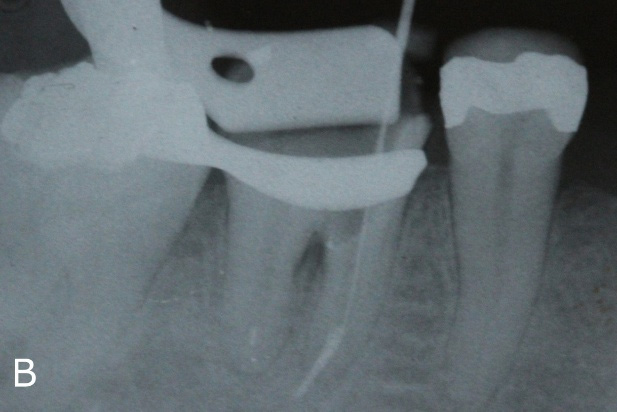

In the same session, the filling material was removed (Figure 3A) with Retreatment files in the distal canal and Hedstroen manual files in the mesial canal, due to suspected fracture of the file in the apical third. The fractured file was confirmed (Figure 3B) with a radiograph. A Calcium hydroxide intracanal dressing was placed during two sessions.

Figure 3: A. Removal of filling material

Figure 3: B. X-ray to confirm the presence of a separated file.